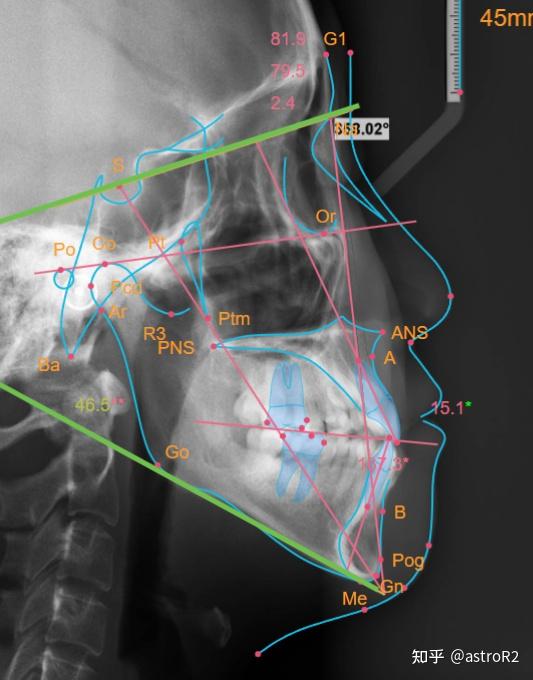

口腔医生须知:头影测量分析 - 知乎

口腔医生须知:头影测量分析